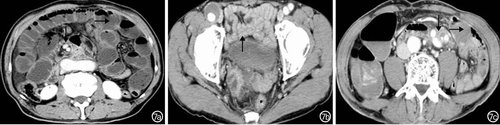

小肠淋巴瘤患者CT检查结果主要表现为局限性或节段性中重度肠壁不均匀性增厚,病变肠壁明显不均匀强化(图1);肠外主要表现为淋巴结、肝、脾肿大。

图1回肠淋巴瘤患者CT检查特征:回肠壁重度不均匀性增厚(↓)、局部肠腔狭窄 1a:平扫肠壁不均匀,低密度;1b:动脉期肠壁明显不均匀强化;1c:静脉期肠壁不均匀强化程度较动脉期增加